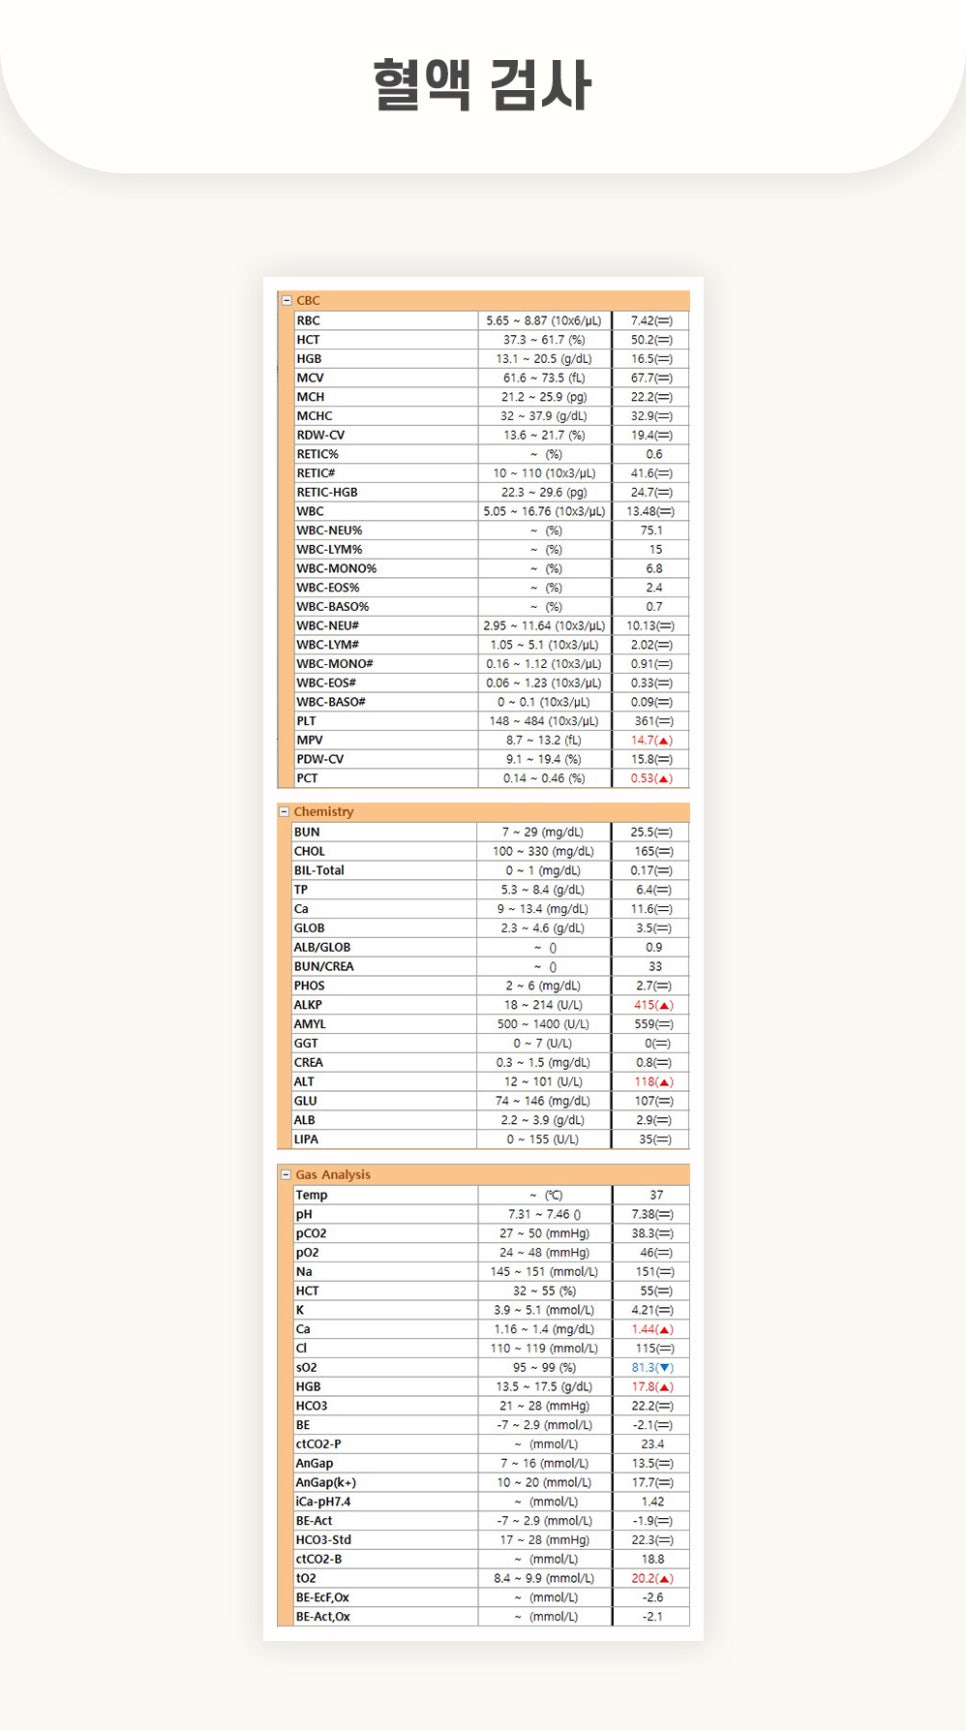

[수술 전 혈액 검사]

혈액검사 결과, CBC부분에서 혈소판 용적을 나타내는 MPV와 PCT가 각 14.7와 0.53로 경도 높게 확인되었습니다.

Chemistry부분에서 간수치를 나타내는 ALKP와 ALB가 각 415와 118로 높게 확인 되었습니다.

또한 Gas Analysis에서는 Ca(칼륨) 1.44로 높은 수치▲sO2(산소포화도) 81.3으로 낮은 수치▲HGB(철분) 17.8로 높은 수치▲tO2(산소 전달량)20.2로 낮은 수치가 확인되었습니다.